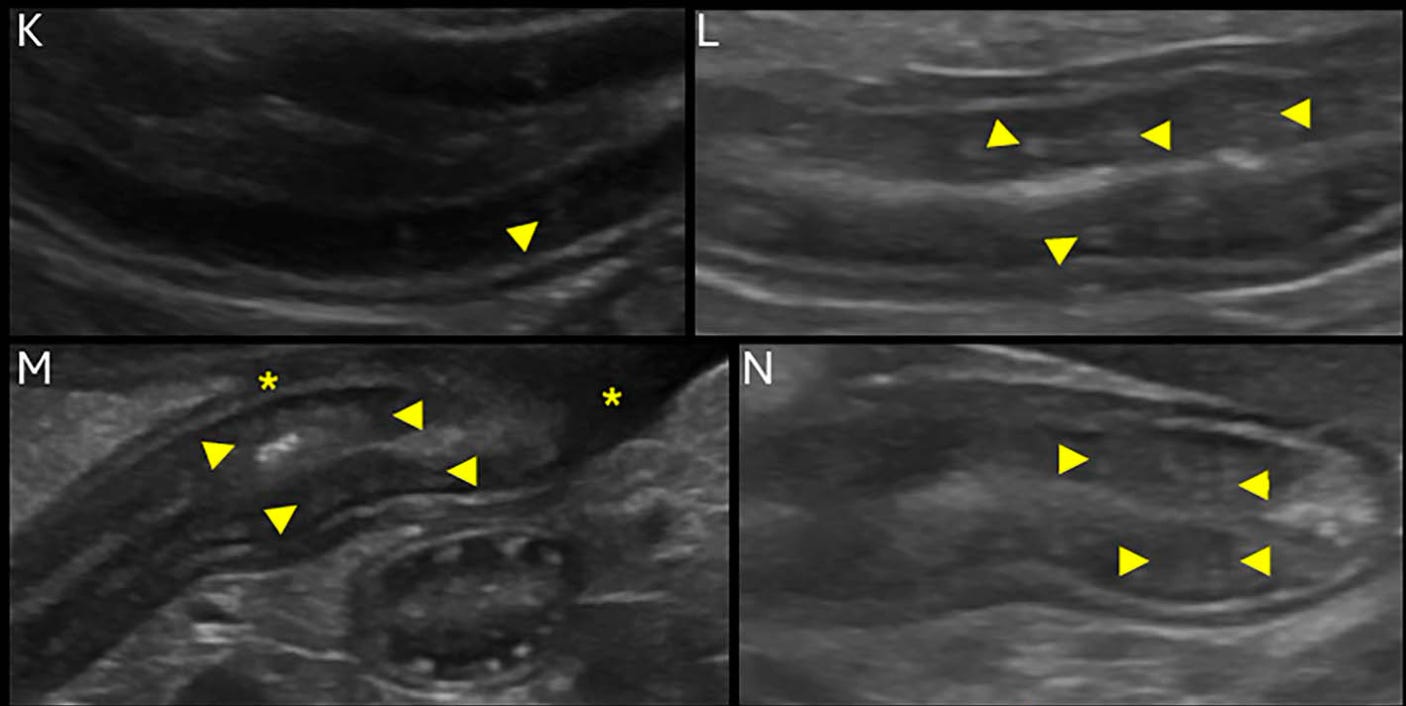

Corrugación intestinal:

Los hallazgos secundarios (ej. linfadenopatía, corrugación del ID) pueden ser muy sugestivos de linfoma GI en oposición a EIC.

Hasta el 93% de los perros con EPP tienen alteraciones ecográficas en el ID, incluyendo líquido libre peritoneal (73-79%), estrías o punteados mucosos (47-91%), linfadenopatía (18-40%) y dismotilidad o distensión del ID (10-23%).

Las estrías hiperecogénicas tienen una sensibilidad del 75% y una especificidad del 96% para la linfangiectasia intestinal que causa EPP, pero los punteados hiperecogénicos son hallazgos no específicos.